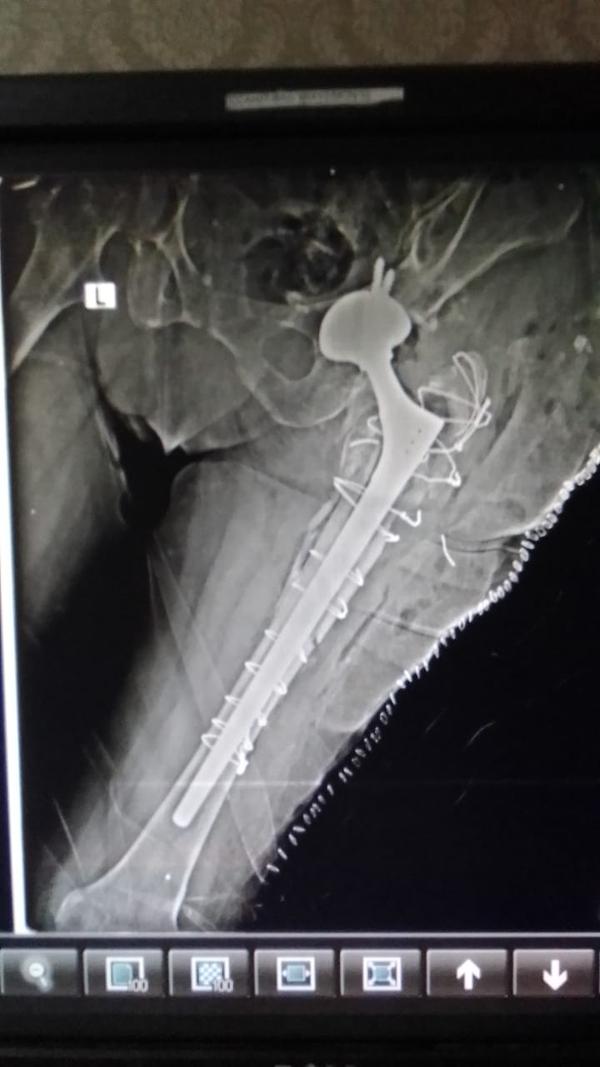

Dr Ajay Randive : IS MS Ortho (Mumbai) MRCSI ( UK) Consultant knee, Hip ,& Spine Surgeon, Dr Ajay Randhive is a eminent Knee, Hip , & Spine Surgeon practicing in to areas Andheri East,Santacruz East. Dr Ajay Randive did his MS Ortho residency from LTMMC, Sion Hospital Mumbai. He did overseas training in UK from 2003 till 2008. He is trained in total Knee Replacement, Hip Replacement, Revision Hip Replacement And Revision Knee Replacement Surgeries. He has worked at The Royal London Hospital. IN London where he worked a clinical fellow in joint Replacement unit. He has carried out more than 5000 Knee Replacement surgeries, 2500 Hip Replacement Surgeries, More Than 500 Revison Knee And Hip Replacement Surgeries 600 Spine surgeries & more than 1500 arthroscopic surgeries (Knee & Shoulder).